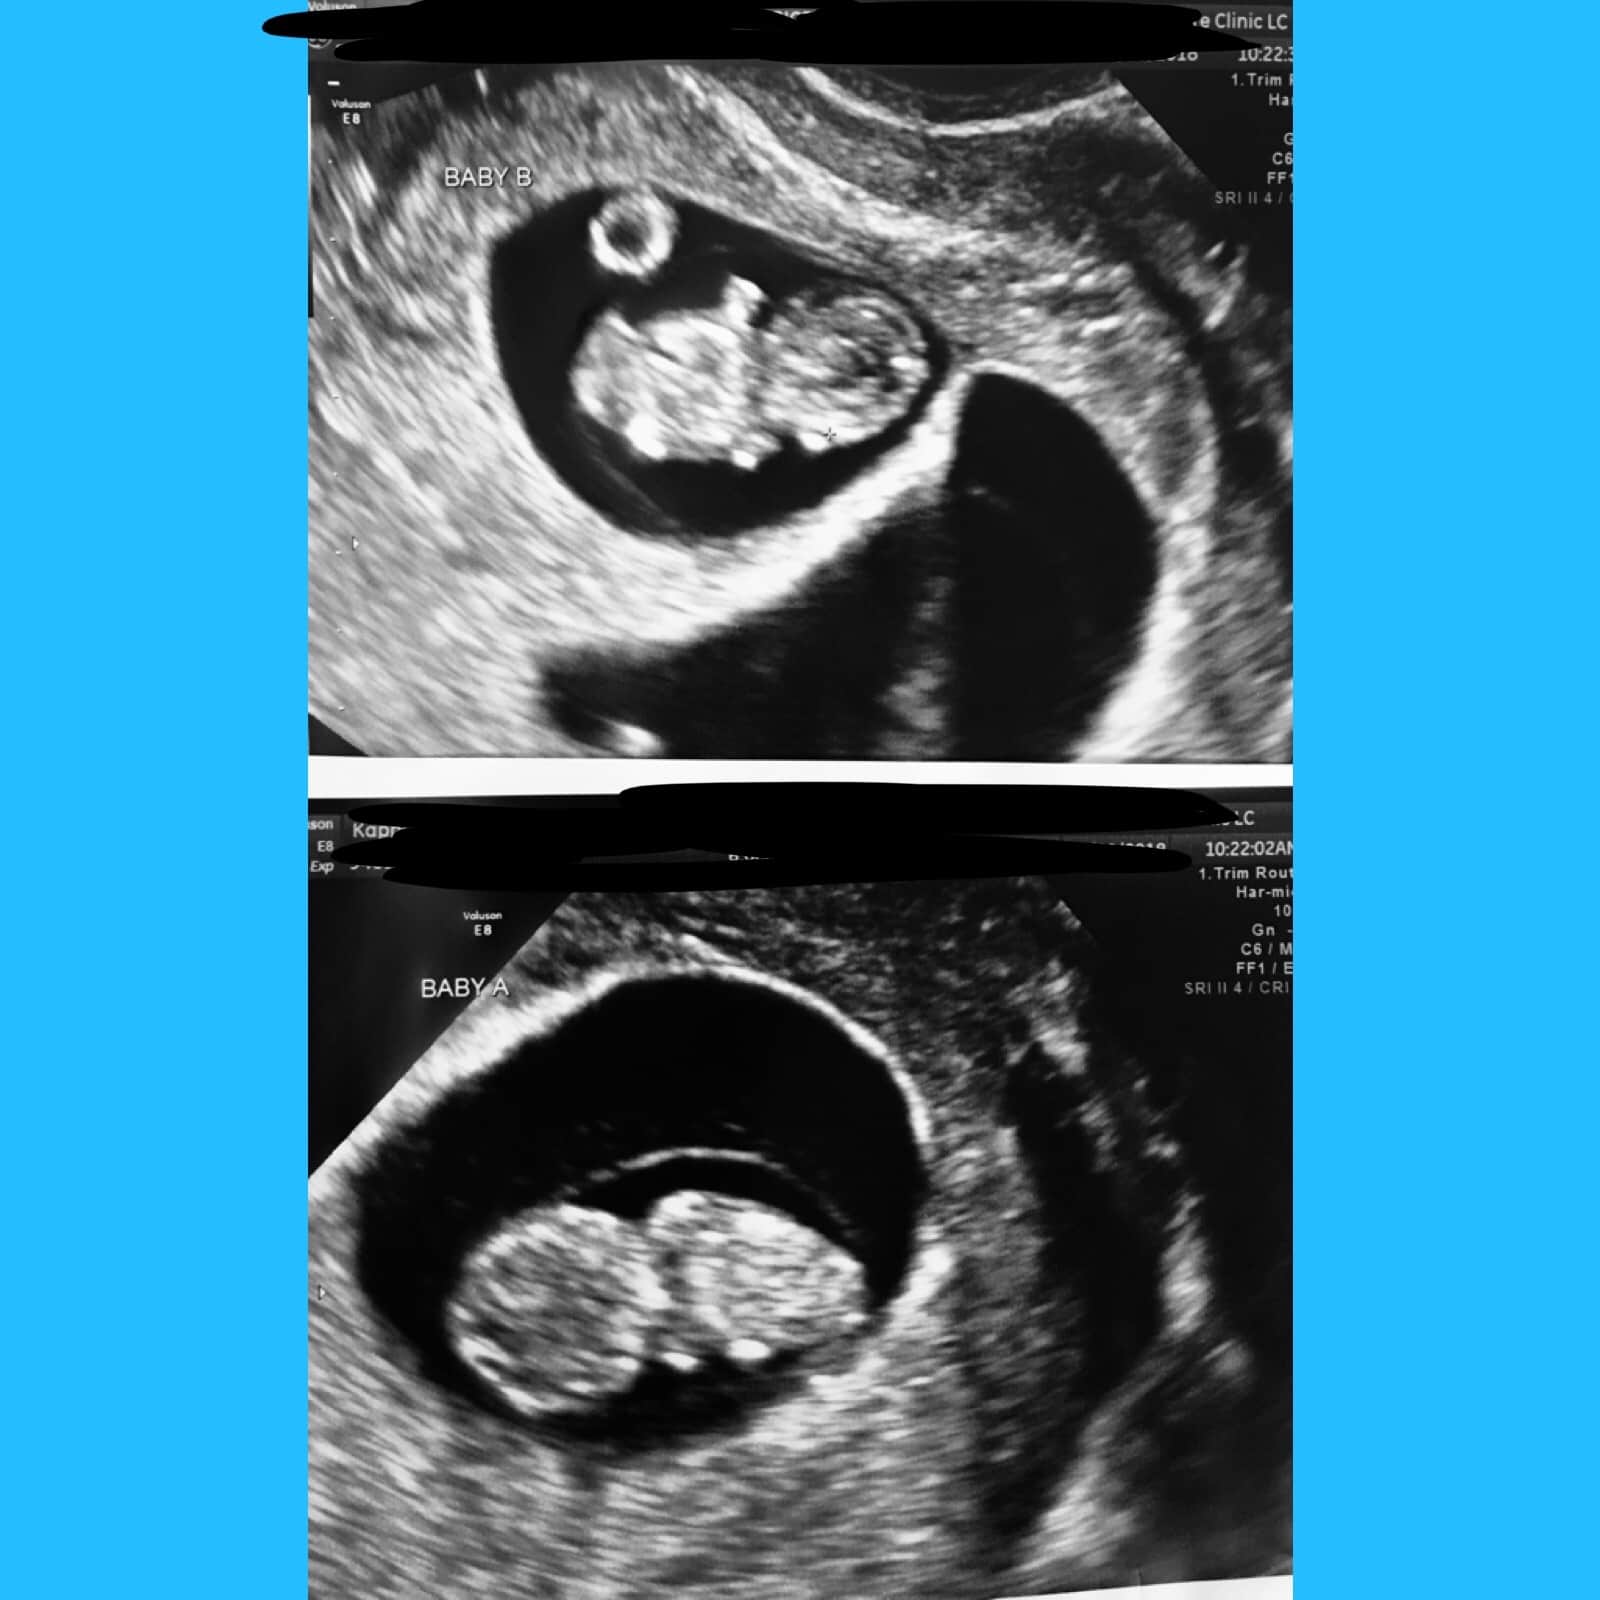

Ultrasound Photos of 9 Weeks Pregnant With Twins